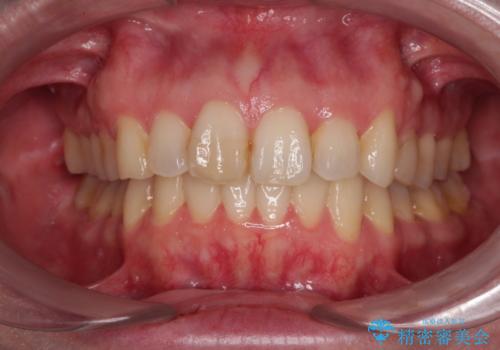

前歯のデコボコを短期間で解消 ワイヤー装置による抜歯矯正

- 上下前歯のデコボコを気にして来院された患者様です。

デコボコが強いため、非抜歯で矯正をすると出っ歯仕上がりとなるため、上下左右の第一小臼歯4本を抜歯することとしました。

当初予定は2年半程度と伝えていましたが、2年にも満たない期間で治療を終えることができました。